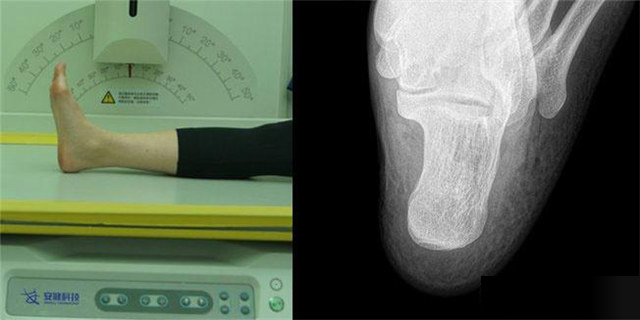

下肢:脛腓骨、踝、足脛腓骨長(zhǎng)骨檢查需要包括--側(cè)的關(guān)節(jié)踝關(guān)節(jié)常規(guī)正+外側(cè)位,特殊時(shí)可選內(nèi)斜位足常規(guī)前后正位+內(nèi)斜位,外傷鑒定等情況,需要負(fù)重的水平側(cè)位(包括足尖和足跟)跟骨側(cè)位+軸位